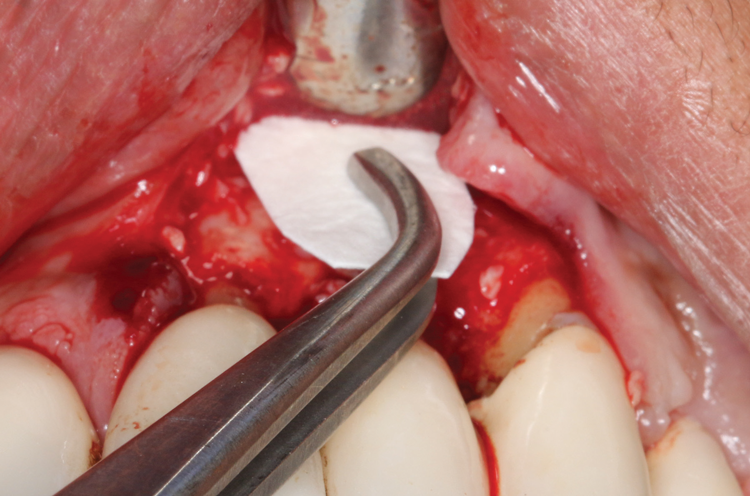

(3.) An envelope reflection was made with no vertical incisions, exposing the entire bony defect affecting the apical portion of the stable implant.

Figure 3

Following infiltration of the facial attached gingiva and palatal area with articaine hydrochloride 4% and epinephrine 1:100,000 (Septocaine®, Septodont [alternatively: Articadent®, Dentsply Sirona; Orabloc®, Pierrel]), an envelope releasing incision was made extending one full tooth over. To prevent trauma to the mucosal tissue, vertical incisions were not made (Figure 3). Incising the mucosa results in the release of prostaglandins and histamine, which increases postoperative discomfort. For this patient, staying in attached gingiva provided excellent control of the flap and allowed clear access to the apical lesion.

This is where the treatment became challenging. First, a curette was used to attempt to remove the granulation tissue from around the apex of the implant circumferentially. This was a difficult endeavor, especially on the palatal aspect of the site. Following curettage, an 810 nm diode laser (NV® PRO3, DenMat [alternatively: Picasso+, AMD Lasers; Gemini, Ultradent]) was used to treat the apical portion of the implant. After the laser tip was initiated using dark occlusal paper (Figure 4), it was used to debride the remaining necrotic tissue and decontaminate the entire site, reducing the bacterial count (Figure 5 and Figure 6).